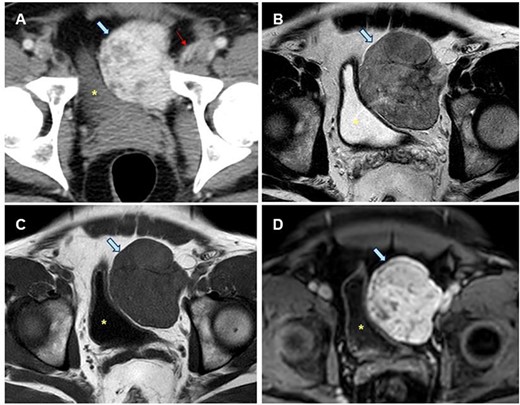

A 43-year-old male patient was referred to hospital with micturition disorders and hypogastric abdominal pain during the previous few months. A computerized tomography (CT) was carried out showing a pre-vesical mass 6 × 5 cm in size with well-defined borders and hypercaptant during the arterial phase (Fig. 1). As an FST was suggested, a fine-needle aspiration (FNA) biopsy was done, but diagnosis was not confirmed.

Radiological study of the pelvic mass. (A) CT scan with intravenous contrast: hypervascular mass (blue arrow). Epigastric vessels give vascular supply, coming from left common femoral artery (thin red arrow). (B, C, D). MRI in late T2-FSE (B), T1-FSE (C) and T1-FAT-SAT GD sequences. Hypointense mass both in T1 and T2 sequences without intravenous contrast suggesting the fibrous origin. It is confirmed in T1 sequence with fat saturation and after intravenous gadolinium administration is homogeneous, in late phase (8 min). Bladder is displaced towards the opposite side (yellow dot).